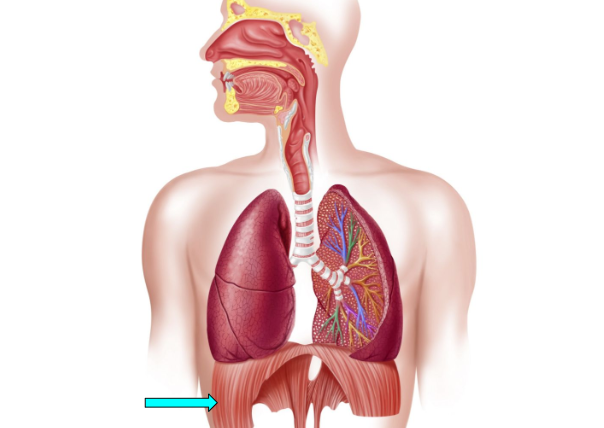

Diaphragm

primary muscle responsible for respiration by contracting to pull down the lungs during inhalation & relaxing during exhalation, changes air pressure in the lungs

Diaphragm (pic)